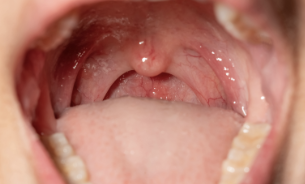

편도염에 걸리면 고열 오한 인후통이 나타나며 인두 근육에 염증이 생기면 침을 삼키기 곤란해집니다.

두통, 전신, 쇠약감, 관절통 등이 신체 전반에 나타나며 혀 표면 및 구강 내에 두껍고 끈적끈적한 점액이 생길 수 있습니다.